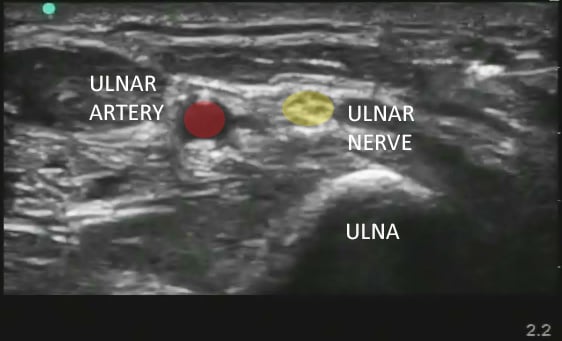

- Directly medial (ulnar side) to the ulnar artery should be a hyperechoic structure representing the ulnar nerve.

- The nerve can be oval or triangular.

- The ulnar nerve sits in the same echogenic fascial plane as the artery.

Figure 1. Sonographic appearance of the ulnar nerve in the mid forearm